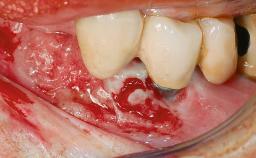

A 77-year-old male patient was referred for the management of frequent and repeated acrylic fracture of his existing mandibular fixed full-arch implant-supported metal/acrylic prosthesis. He also complained about softtissue soreness and the lack of retention and stability of his maxillary removable partial metal/acrylic prosthesis. Both prostheses had been delivered two years previously as part of his full-mouth rehabilitation (caries, tooth wear, tooth fracture). His medical history revealed high blood pressure, controlled with the use of antihypertensive medication.